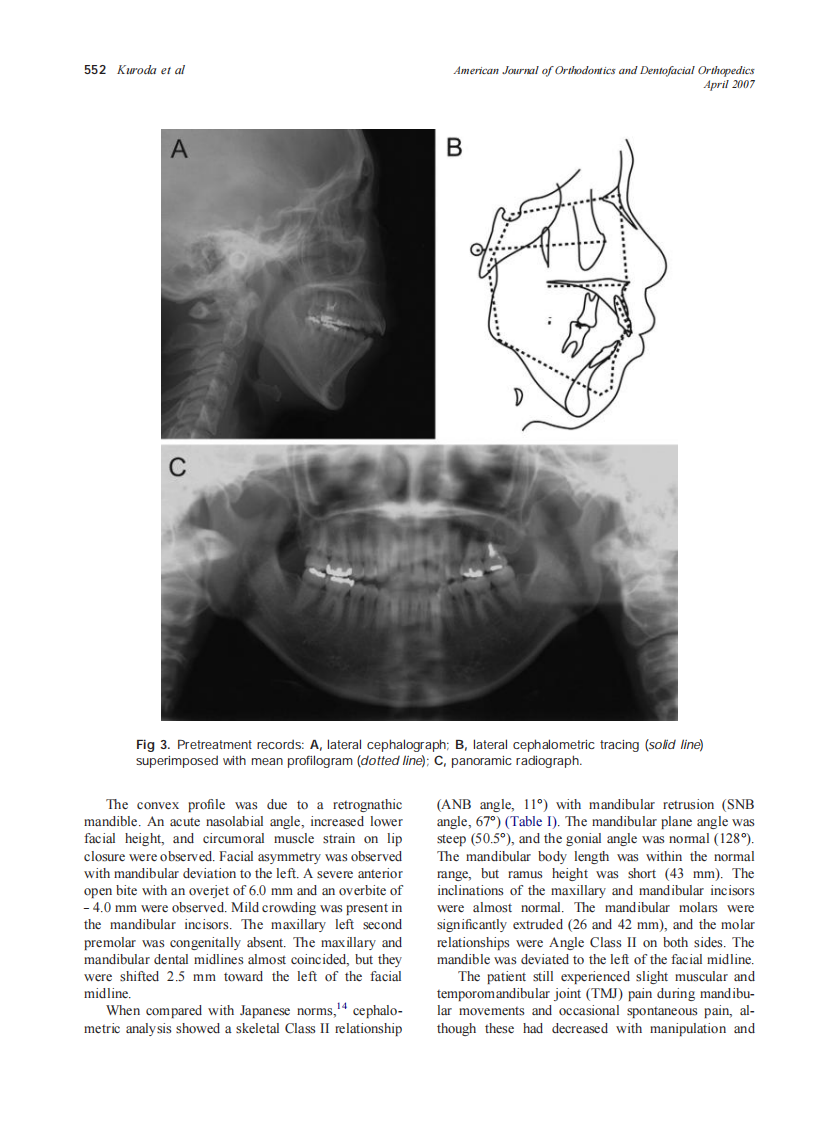

2007_131_4_550_560_Kuroda.pdf